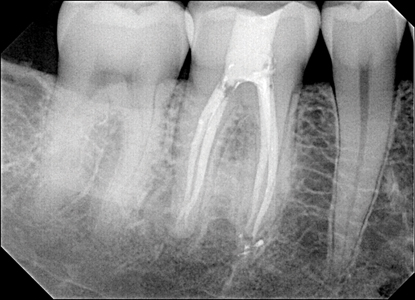

THE FUTURE

The Endodontic Triad is alive and well. Many endodontic companies and inventive endodontists are investigating more predictable ways to treat endodontic disease. For example, I can report as a Dentsply Sirona KOL leader/designer that much energy and innovation is being given to the 2021 launches of products addressing all 3 parts of the Endodontic Triad as well as sealers. Peering into the future, sometimes innovations can become fantasies, and sometimes these mysterious and abstract fantasies become reality. (Fig. 3) But the “X” in 100% − X is about to become a smaller “x.”

Fig. 3A

Fig. 3B

Fig. 3C

Fig. 3D

Fig. 3E

Fig. 3F